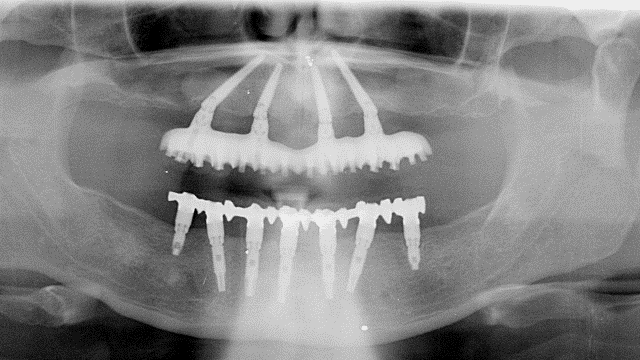

L'implantologia diventa quindi in questo ambito riabilitativo l'alternativa per eccellenza, in quanto permette il ripristino totale della funzione masticatoria con denti fissi. Tale protesi completa con impianti, è conosciuta come "Toronto Branemark Bridge" e prevede secondo il protocollo svedese originale, l'inserimento di un numero adeguato di impianti nelle arcate ed in posizioni idonee tali da sostenere meccanicamente la successiva protesi fissa ed il relativo carico masticatorio (almeno 6 nell’arcata superiore e 5 nell'inferiore). Relativamente al numero di impianti che sono necessari per soddisfare le condizioni meccaniche utili ad applicare su di essi una protesi fissa, negli ultimi anni è venuta a mancare la consueta chiarezza. Come detto poco sopra il protocollo svedese originale recita testualmente:

nell’arcata superiore “almeno sei impianti nell’area della premaxilla, ovvero l’area ossea compresa tra i seni mascellari da entrambi i lati”

nell’arcata inferiore “cinque impianti nella regione del mento, entro i limiti anatomici determinati dal nervo mentoniero”.

Tuttavia circa quindici anni fa ad opera di un gruppo di professionisti Portoghesi, diretti dal dottor Paul Malò, venne proposta una riduzione del numero di impianti rispetto al protocollo originale con la supposta intenzione di semplificare il trattamento stesso. Prese cosi vita il concetto “All On Four” che limitava l’inserimento a quattro impianti sia nel mascellare superiore che inferiore per una riabilitazione protesica fissa tipo “Toronto Bridge”. (6)

In realtà molti anni prima, circa venticinque anni fa, Branemark assieme ad altri ricercatori di primissimo piano, dimostrò effettivamente la possibilità di limitare a quattro il numero di impianti da inserire in entrambe le arcate per la soluzione dell’edentulia completa.(7) La grande differenza tra l’enunciato di Branemark e le proposte del gruppo “Malò” risiedono nel fatto che in questo studio Svedese era consentita la riduzione di numero degli impianti ma solo nel caso che le quantità ossee fossero ridotte e che pertanto non sia possibile inserire un numero di impianti superiore, ma se al contrario, i volumi ossei residui lo consentono, il numero di impianti da inserire deve rimaneva quello del paradigma classico ovvero cinque inferiori e almeno sei superiori.